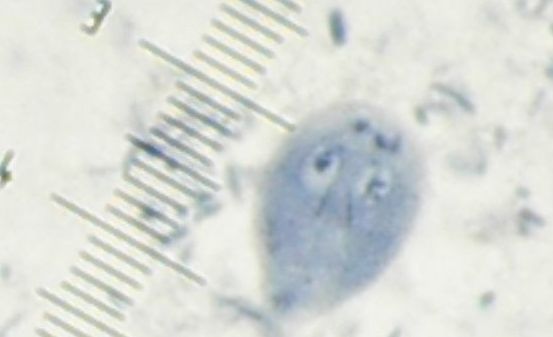

11. A patient with diarrhea is found to have the following organisms in her fecal specimen.

What is the likely diagnosis ?

A sample of the discharge is taken from the cervix and examined under a microscope.

What is the likely seen under the microscope ?